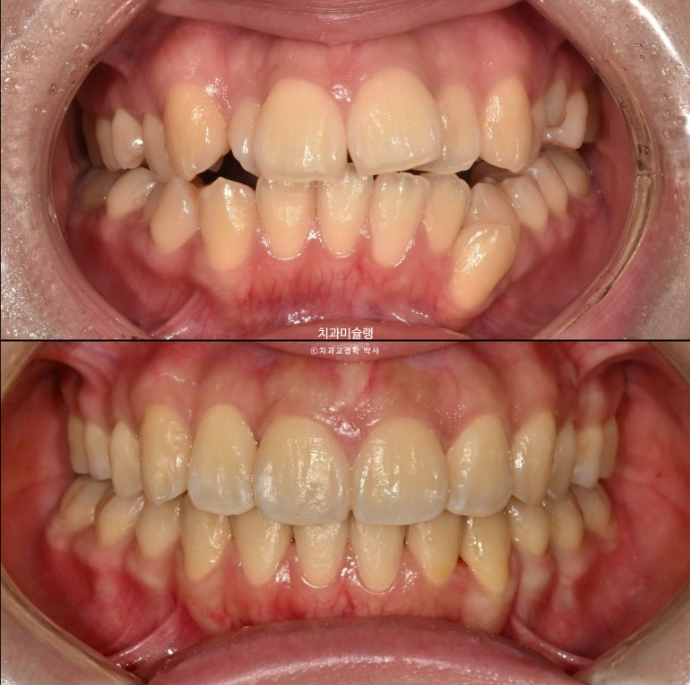

23.10~26.01

개방교합이 해소되어 잘 물립니다

중심선 불일치는 해결이 되었습니다.

교합이 좋습니다.